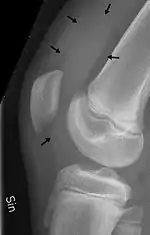

Traumatic effusion of the right knee, with swelling lateral to the kneecap marked by an arrow |

An X-ray is useful to verify that there is no break or dislocation when there is a history of trauma. May show signs of osteoarthritis.